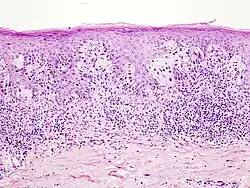

Czerniak guzkowy w obrębie twarzy

Obraz histopatologiczny czerniaka guzkowego

Czerniak guzkowy

Jest to drugi co do częstości podtyp czerniaka, stanowi około 10–15% wszystkich przypadków czerniaka[87][82]. Charakteryzuje się pionowym wzorcem wzrostu. Czerniak guzkowy może występować w dowolnym miejscu, w porównaniu do czerniaka szerzącego się powierzchownie częściej występuje na tułowiu, głowie, szyi i kończynach dolnych[87]. Klinicznie jest szybko rosnącym guzem[88]. Czerniak guzkowy najczęściej powstaje de novo, a znacznie rzadziej w istniejącym wcześniej znamieniu[89]. Nowotwór ten statystycznie częściej niż czerniak szerzący się powierzchownie dotyka osoby starsze[87].

Makroskopowo przedstawia się jako szybko rosnąca grudka lub blaszka. Zmiana bywa polipowata, a rzadko nawet uszypułowa. Guz jest symetryczny i dobrze odgraniczony, o gładkiej powierzchni[88]. Zmiana cechuje się kolorem czarnym lub niebieskim, możliwa jest postać amelanocytowa, która przybiera kolor różowoczerwony[87]. Rozmieszczenie barwnika często nie jest symetryczne, choć bywa regularne[88]. Często jest obecne owrzodzenie guza[87][90].

Mikroskopowo jest podobny do czerniaka szerzącego się powierzchownie, jednak nie obserwuje się horyzontalnego śródnaskórkowego rozprzestrzeniania się. Komórki nowotworowe znajdują się w skórze właściwej, komponenta naskórkowa jest zależna od obecności czerniaka w skórze właściwej i nie istnieje samodzielnie[88]. Pokrywający naskórek jest scieńczały, zamazany lub owrzodziały[87]. Guz jest zbudowany z masywnych gniazd melanocytów[91]. Wyróżnia się typy o komórkach przypominających komórki nabłonkowe, typ o komórkach wrzecionowatych i typ mieszany[92][90]. Melanocyty zwykle są pleomorficzne i często stwierdza się kilka typów komórek[88]. Mitozy są liczne, często obecna jest martwica atypowych melanocytów[91].